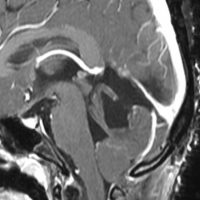

小さな松果体奇形腫です。

OTAでこの奇形腫を見ようとする場合に,テントを静脈洞交会の低い位置まで切断しなければ,直静脈洞の横から松果体部をみることはできません。また,黄色の矢印の方向に視野が入るので,まず最初に邪魔になるのは小脳上極です。上小脳層を左右ともに十分剥離すると,小脳が可動化して,その向こうに,precentral cerebellar veinが見えます。このveinをガレン大静脈への流入部から小脳前面に沿って剥離していくと,小脳上極がさらに可動化して松果体への視野が開ます。

松果体腫瘍の手術では,中脳背面を見る必要があります。特に上丘とそれに連続する後交連 posterior commissureを十分に観察するために周囲組織の剥離を行います。具体的には迂回槽と下丘の周囲のクモ膜組織を剥離します。対側中脳と迂回槽を見る時に妨げになるのが,緑の矢印で示した直静脈洞です。テントが長く切断してあって直静脈洞が大脳鎌と一緒に動かせると対側を見るのがとても簡単になります。